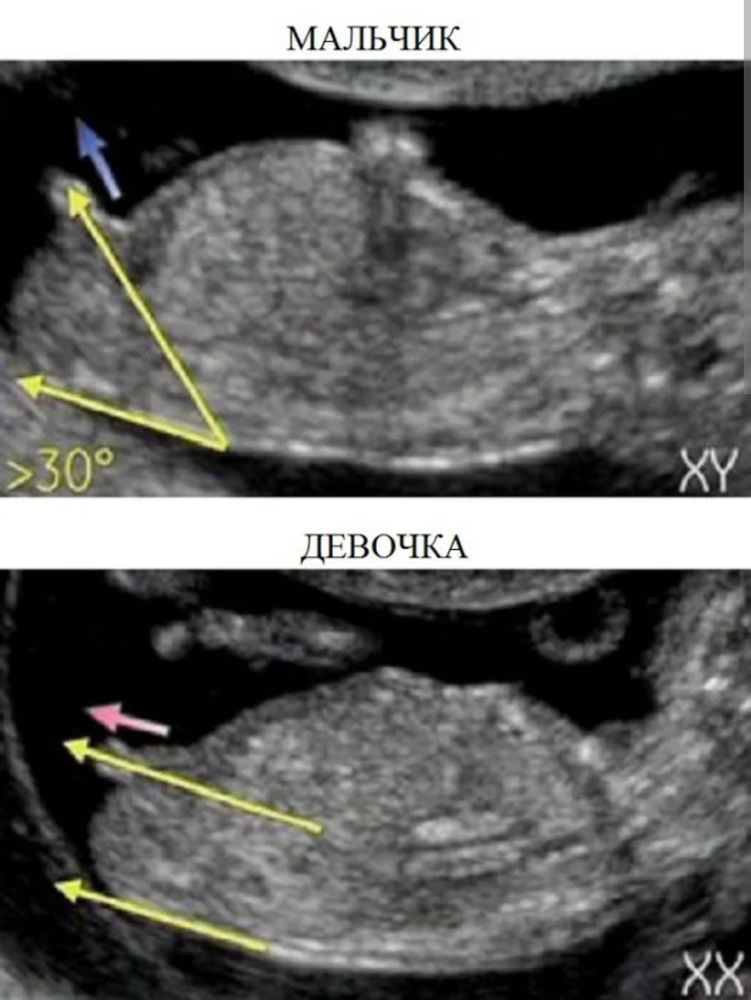

Мария, ну, я не спец в этом вопросе. Просто можно посмотреть фото в интернете, там разные углы половых бугорков у мальчиков и девочек. Из этого и сложился ответ) А так: все могут ошибаться, и врачи в том числе)Но Вы правильно рассуждаете: главное, чтобы малыш был здоров, а остальное всё мелочи. Удачи Вам и лёгкой беременности!✨

Изображение Изображение Изображение Последняя фотография с интернета❤️ у нас девочка

Да, это сынок, я так вижу. Относительно позвоночника - угол.

Светик, это девочка. Там половые губы у меня такая же малышка сказали что скорее девочка и я верю ведь тот врач не ошибается ) уже давно не ошибается) когда мальчик там нет 2 отражений и угол к верху) а тут по середине и половые губы чётко видны)